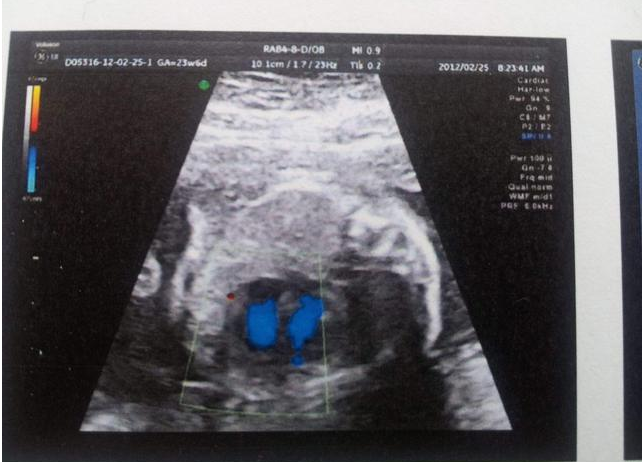

通常來說,將近足月時胎盤成熟度都在2級和3級,這很正常。但是,如果懷孕20周左右,胎盤成熟度達到3級,就表明胎盤功能減退了。衡量胎盤功能是否減退,也就是常說的“胎盤老化”,主要看胎盤的發育成熟度是否超過了妊娠月份。